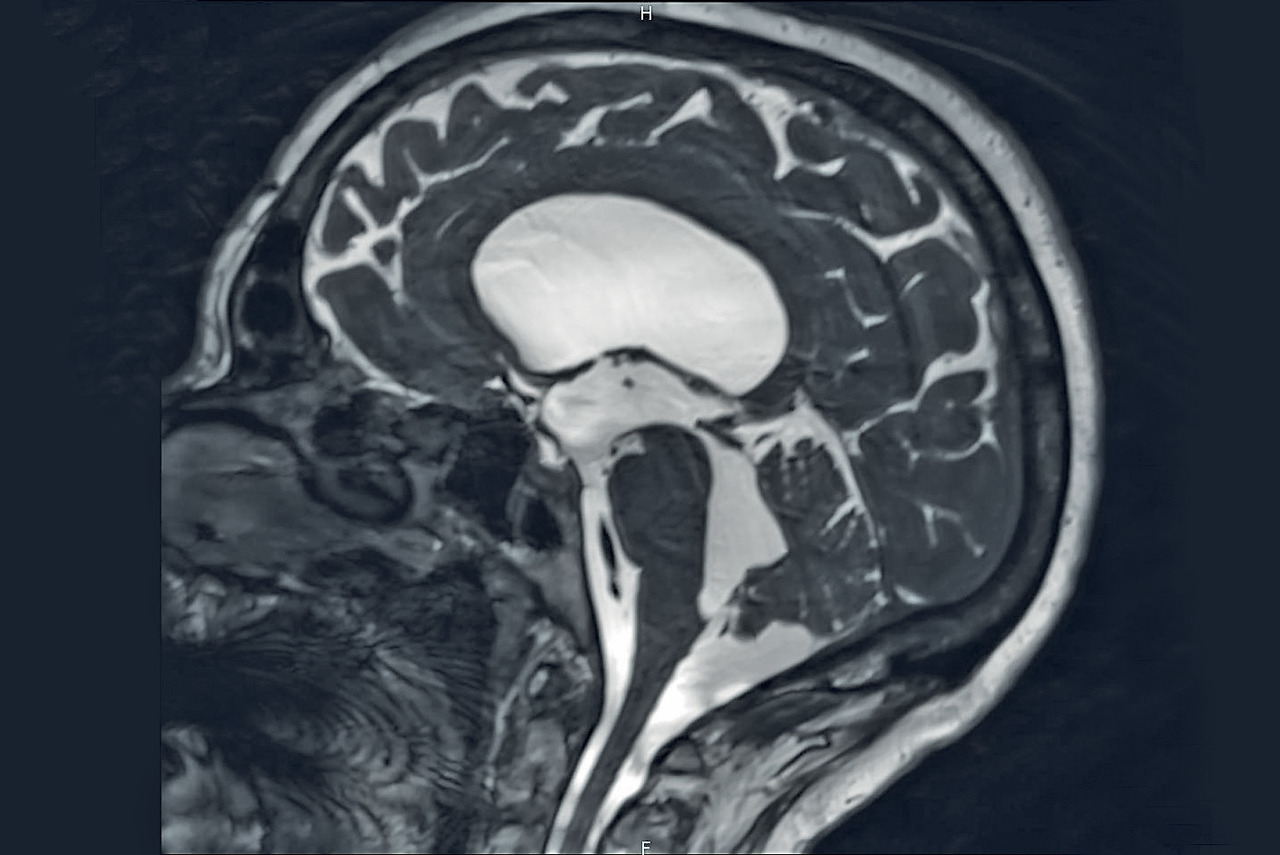

En aigu, le scanner cérébral sans injection de produit de contraste est l’examen de choix. Il montre la taille des ventricules et une éventuelle cause hémorragique. Chez les malades ayant une dérivation ventriculaire interne, il doit être comparé aux images antérieures de référence.

L’IRM cérébrale est nécessaire en cas d’hydrocéphalie triventriculaire (les 2 ventricules latéraux et le 3e). Elle met en évidence un obstacle à l’écoulement du LCR (+++), son flux étant analysé grâce à des séquences dynamiques. Après chirurgie, on y contrôle l’efficacité d’une procédure de ventriculocisternostomie. Elle complète le bilan en cas de tumeur cérébrale et confirme une imperforation des trous de Magendie et/ou de Luschka (orifices de sortie du 4e ventricule ; fig. 2), essentiellement congénitale (malformation de Dandy-Walker, agénésie ; encadré).